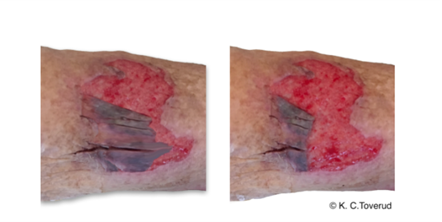

Skin tear

- Skin tear er et traumatisk sår, forårsaget af mekaniske kræfter, og opstår fx i situationer med forflytning, patientpleje og fjernelse af produkter med klæber på huden. Skin tear er en hyppigt forekommende tilstand, som ofte omtales som hudafskrabning, hudlæsion med hudlap eller adskillelse af hudlag.

- Ældre er i særlig risiko for skin tears, da huden ændrer sig med alderen, hvor huden bliver tyndere, oftere er dehydreret og mister sin elasticitet. Samtidigt er der mindre subcutant fedt, reduceret blodforsyning og hudens tilhæftningsevne mellem de forskellige lag er mindsket. Dette giver en skrøbelig hud med stor risiko for skin tears.

Derfor har vi i VAR udarbejdet tre nye procedurer og videnskapitler til forebyggelse og behandling af skin tears.